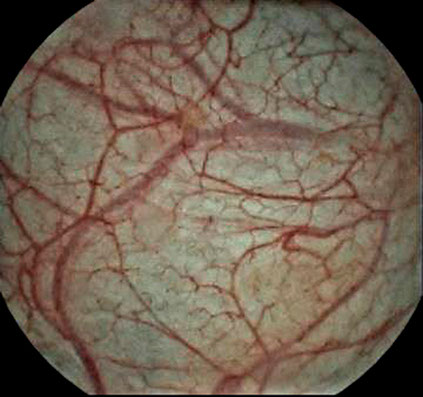

Image Enhancement

ICE RGB Mode separates different RGB spectrums, gives you a more detailed view for mucosa and capillaries.